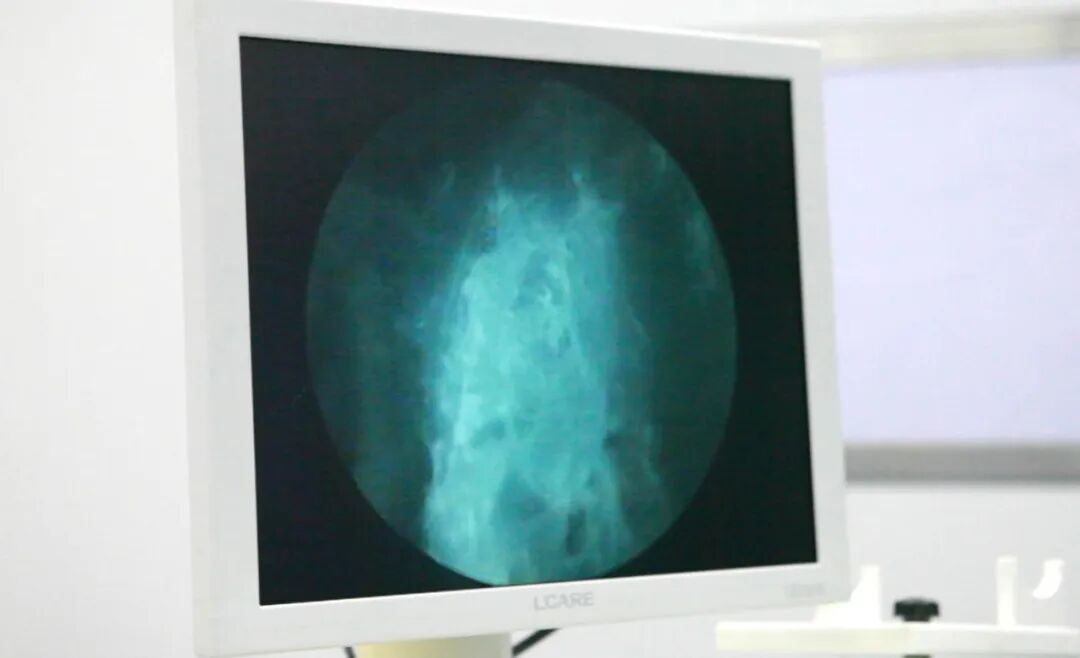

高功率蓝激光前列腺增生汽化术进行中

入院后,经过详细的术前讨论和准备,综合外科团队应用医院引进的蓝激光成功为张大爷进行经尿道蓝激光前列腺增生汽化术,手术非常顺利,仅用20分钟,术中基本无出血。